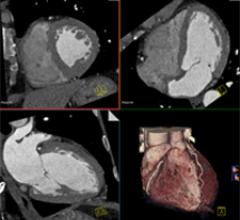

November 3, 2011 — Infinitt North America announced that their Xelis Cardiac product has received clearance from the U.S ...

CTA is one of the most complex procedures routinely performed on a CT scanner. A successful CTA exam requires ...

Computed tomography angiography (CTA) is one of the most complex procedures routinely performed on a CT scanner. A ...

While CT angiography (CTA) is a complex procedure, Philips Ingenuity CT has advanced features to simplify CTA planning ...